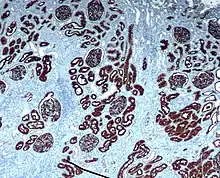

Microscopic cross section of the renal cortex

CD10 immunohistochemical staining of normal kidney. CD10 stains the proximal convoluted tubules and glomeruli.